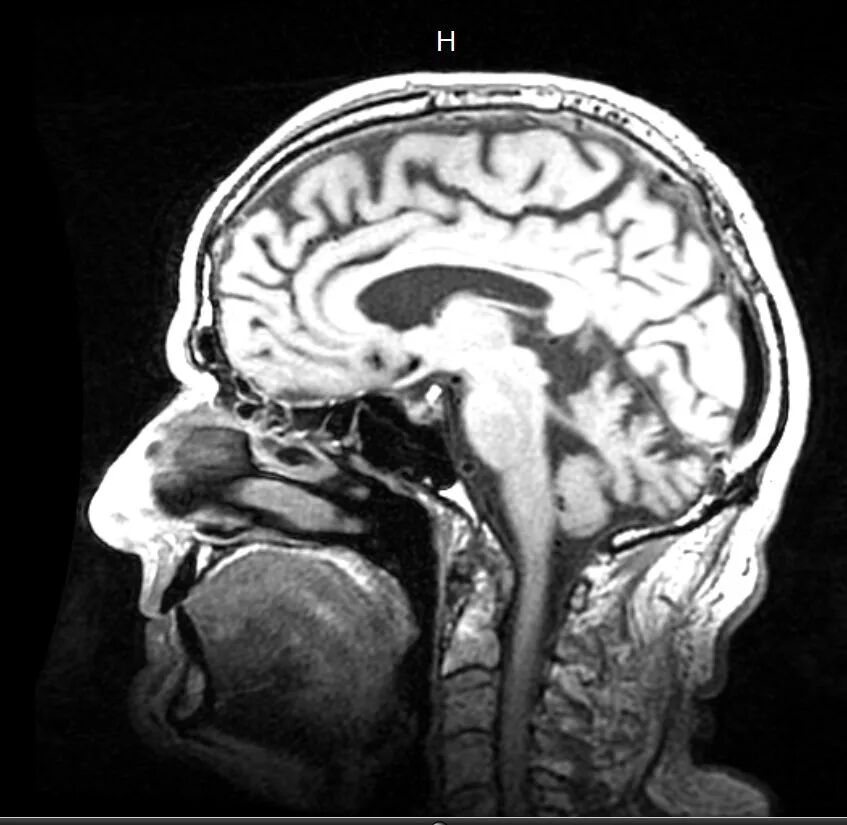

三.双相患者的大脑和健康患者一样吗?人们是如何研究它的?

近年来双相障碍的神经影像学研究进展非常快,相关研究结果对探索双相障碍的发病原因及其发病机制提供了非常重要的生物学证据。双相障碍的神经影像学检查技术,包括结构性影像学和功能性影像学技术,前者包括计算机体层摄影术(CT)磁共振成像(MRI)后者包括单光子发射计算机断层扫描(SPECT)正电子发射计算机扫描(PET)功能性磁共振成像(Functional MRI)等。

双相障碍患者的大脑结构异常主要包括前额叶,边缘系统全部和中部脑区局部灰质的容积减少及白质结构变化,非特异性的脑室扩大,白质高信号增加等异常表现,发病年龄早的患者表现往往更为明显。碳酸锂对双相患者大脑结构改变有显著作用,可以增加内侧额叶和前扣带回的容积,但药物对局部大脑结构的具体作用机理尚未明确。